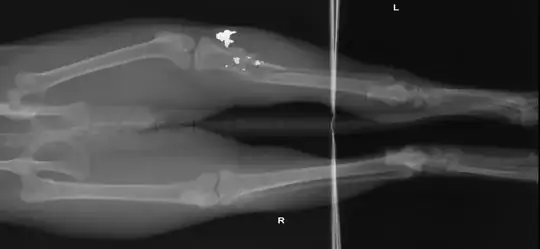

What are the white/opaque shards in these cat leg X-rays?

In the left proximal tibia and fibula there are highly comminuted fractures and mild displacement, moderate soft tissue swelling and a large amount of metal debris at the fracture site.

The left hip is luxated and abnormal. The femoral head and neck are abnormally shaped and have moderate particular new bone formation on all aspects. Not other abnormalities are detected.

1. Comminuted mildly displaced proximal left tibial and fibula fractures tue to a projectile injury (gunshot of some type).

2. Luxated left hip with abnormal conformation and moderate osteoarthrosis. The chronic changes in this hip are likely due to avascular necrosis of the femoral head and neck and/or a proximal physeal fracture. Hip dysplasia cannot be completely ruled out; however it is less likely since there is normal conformation in the right hip.

I'm surprised that a pellet could shatter multiple bones like that. It must have been a very unlucky shot.